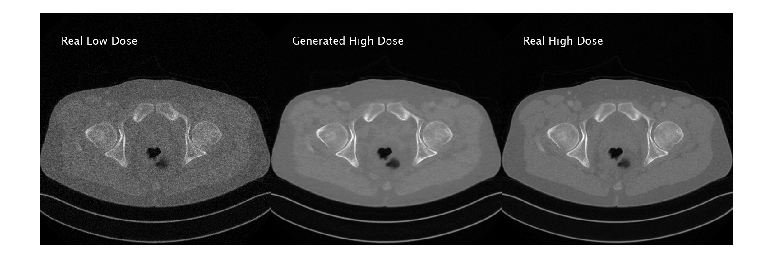

Generate New Images Using Test Data

Define the number of test images to use for calculating quality metrics. Randomly select test images to display.

numImagesToDisplay = 3;

idxImagesToDisplay = randi(numel(filesTestHD),1,numImagesToDisplay);

for idx = idxImagesToDisplay

dsTestHD = partition(timdsTestHD,Files=idx);

imageHD = read(dsTestHD);

imageHD = imageHD{1};

dsTestLD = partition(timdsTestLD,Files=idx);

imageLD = read(dsTestLD);

imageLD = imageLD{1};

imageLD = dlarray(imageLD,"SSCB");

if canUseGPU

imageLD = gpuArray(imageLD);

end

% Generate high-dose image from low-dose image

imageHDGenerated = predict(genLD2HD,imageLD);

imageHDGenerated = gather(extractdata(imageHDGenerated));

imageLD = gather(extractdata(imageLD));

imageResultsLDReal = insertText(rescale(imageLD),[40 40],"Real Low Dose", ...

FontSize=24,TextColor="white",BoxOpacity=0);

imageResultsHDGen = insertText(rescale(imageHDGenerated),[40 40],"Generated High Dose", ...

imageResultsHDReal = insertText(rescale(imageHD),[40 40],"Real High Dose", ...

figure

montage({imageResultsLDReal,imageResultsHDGen,imageResultsHDReal},Size=[1 3]);